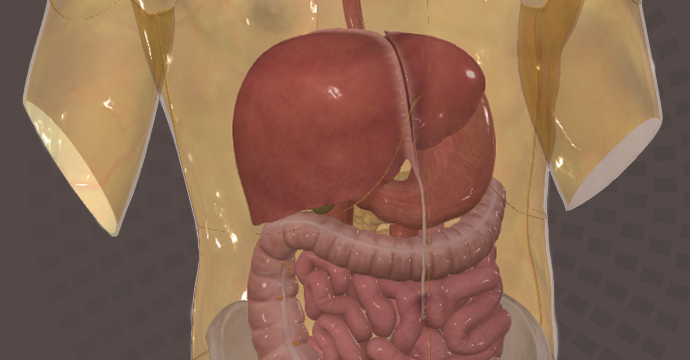

Take your understanding of human anatomy to the next level. Our comprehensive resources combine detailed information and stunning illustrations!

Enhance your studies for a truly dynamic learning experience. Explore interactive anatomy models from Complete Anatomy. Start mastering anatomy today with our free anatomy flashcards designed for quick review on the go.